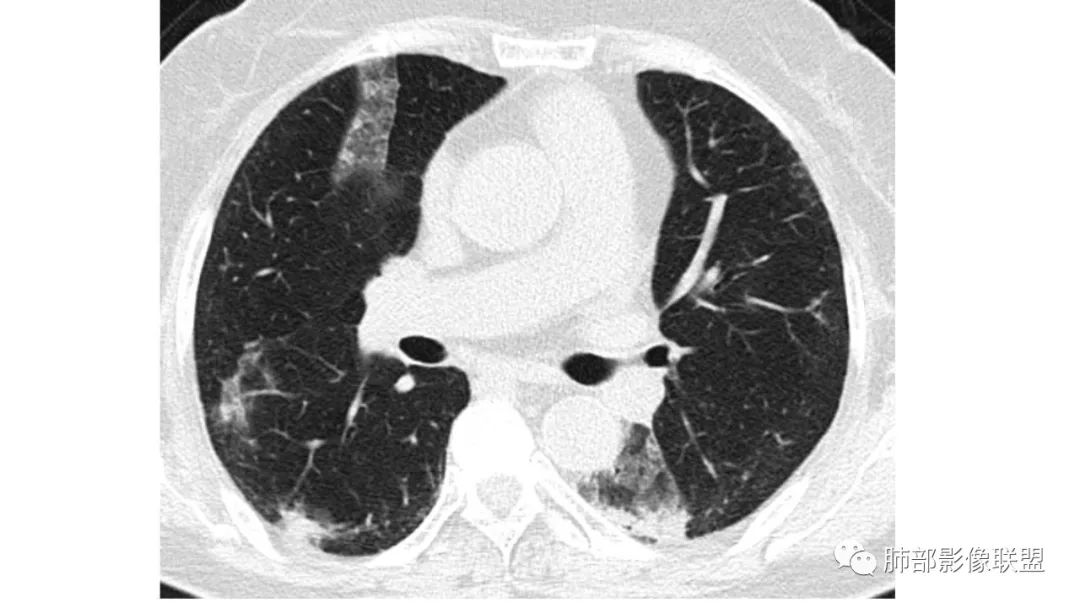

二、肺炎型

2、病灶常有一个主病灶,常位于下肺。后沿气道播散为多发病灶。

3、重力作用,叠瓦征。近叶间裂因重力效应,呈膨隆改变。

4、增强后不均匀强化,存在低强化区呈弱强化或无强化,因此可见“血管造影征。”血管毛糙与肺炎有统计学差异。

5、支气管粗细不均,呈“枯树枝征”,但与肺炎这一点鉴别不具有统计学差异。可发生支气管扩张

6、空腔形成,部分蜂窝状改变。

8、斑片常伴有结节,边缘清楚GGO或欠清楚。